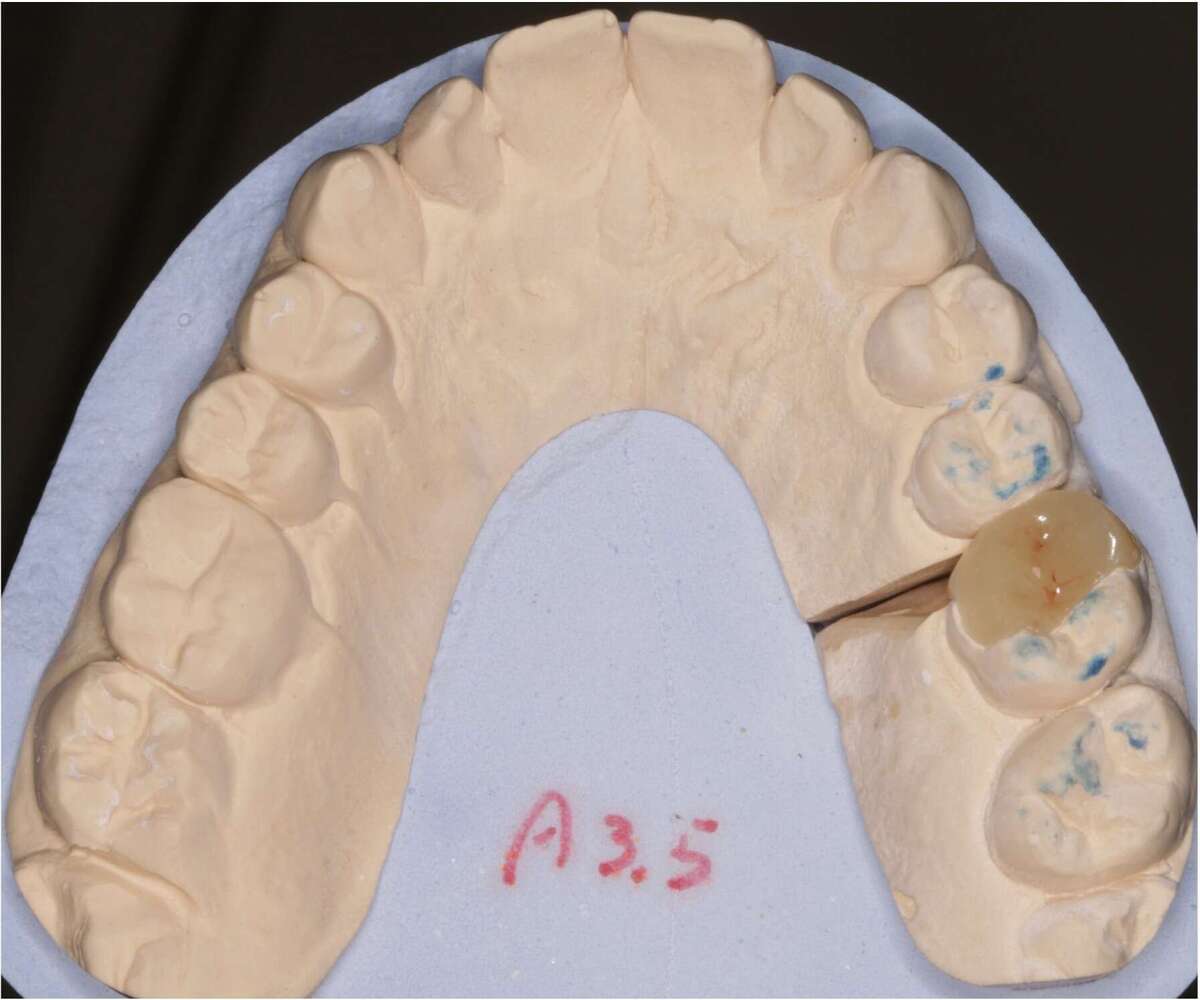

Choix de la teinte et empreinte

Choix de la teinte

Réalisation d'un onlay en céramique par le laboratoire